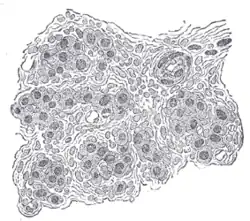

Buňky karotidového tělíska a okolo nich hustá síť vlásečnic

Je tvořeno buňkami I. typu a buňkami II. typu, obě jsou navíc omývány fenestrovanými vlásečnicemi. Buňky II. typu jsou spíše jen podpůrné. Buňky I. typu obsahují množství váčků s dopaminem, serotoninem a adrenalinem. Pokud je zjištěna nízká koncentrace kyslíku, vysoká koncentrace CO2 či nízké pH (souvisí s obsahem CO2), je signál předán nervovým zakončením směřujícím do centrální nervové soustavy.